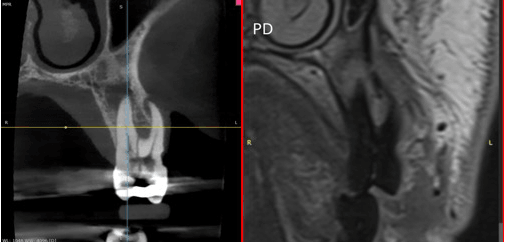

Inselspital Bern has pioneered the use of 7-Tesla Magnetic Resonance Imaging (7T-MRI), a cutting-edge tool enhancing diagnostic capabilities in neurology. Dr. Piotr Radojewski from the University Institute for Diagnostic and Interventional Neuroradiology elaborates on its transformative potential in an interview. The ultrahigh-field 7T-MRI provides unparalleled imaging resolution, unveiling subtle brain structures and processes previously undetectable. Its applications are extensive, from detecting minor anomalies to evaluating complex conditions like epilepsy, multiple sclerosis (MS), and cerebrovascular diseases. For instance, 7T-MRI allowed the accurate diagnosis of a cortical dysplasia in an epilepsy patient, paving the way for targeted surgical intervention. Such advancements exemplify its superiority in identifying lesions invisible to standard 3T-MRI. In MS research, 7T-MRI has revealed cortical lesions and paramagnetic rim lesions, offering critical insights into disease progression and therapy optimization. Additionally, it is pivotal in diagnosing challenging conditions like CNS vasculitis and evaluating the safety of novel Alzheimer’s medications by identifying amyloid-related imaging abnormalities. Despite its promise, 7T-MRI is not yet a routine tool, given limited availability and ongoing evidence accumulation. Dr. Radojewski envisions its integration into standard clinical practice, akin to the historical trajectory of 3T-MRI, emphasizing the importance of collaborative feedback loops between clinicians, researchers, and technologists. This innovation underscores Inselspital’s commitment to leveraging technology for enhanced patient outcomes and sets a benchmark for the future of neuroimaging.